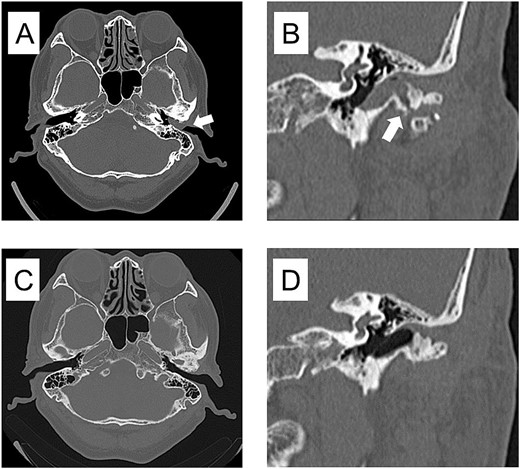

Based on these findings, a clinical diagnosis of TMJ osteoarthritis and TMJ ganglion was made. In July 2017, the mass in the external auditory canal ruptured, and the swelling disappeared; however, the mass flared up again in September, and in October 2017, the left external auditory canal was completely occluded. Axial-section CT showed occlusion of the left external auditory canal, and coronal-section CT showed a bone defect extending from the TMJ to the external auditory canal. (Fig. 4A, B). The patient requested surgery and underwent a left-sided mandibulectomy under general anesthesia and auditory canalplasty performed in December. Intraoperatively, the TMJ was approached via a left preauricular incision, the joint space was opened, and the mandibular head was removed via an 8-mm horizontal osteotomy. During surgery, the surrounding calcified material was removed, as was the anteriorly dislocated articular disc because it was deformed (Fig. 5). Subsequently, transcanal endoscopic ear surgery was performed by otolaryngologist. A skin incision was made before the mass, and a clear jelly-like fluid was found. After the surgery, the patient had intermaxillary fixation for 3 days and began opening training on the fourth day. The opening size improved to 48 mm on the 10th day, and the patient was discharged 13 days after the surgery.

CT imaging findings when the mass was enlarged and the ear canal was obstructed and 3 years after surgery. (A) Axial section CT shows occlusion of the left external auditory canal. (B) Coronal section CT shows a bone defect from the temporomandibular joint to the external auditory canal. (C) Axial section of postoperative 3 years CT shows resolution of the mass in the external auditory canal. (D) Coronal section of postoperative 3 years CT shows restoration of bone defects from the TMJ to the external auditory canal.

Three years postoperatively, the swelling in the left external auditory canal did not recur (Fig. 4C, D), the shape of the resected left temporomandibular head had stabilized, and the left TMJ did not develop any opening disorder, deviation, or pain.